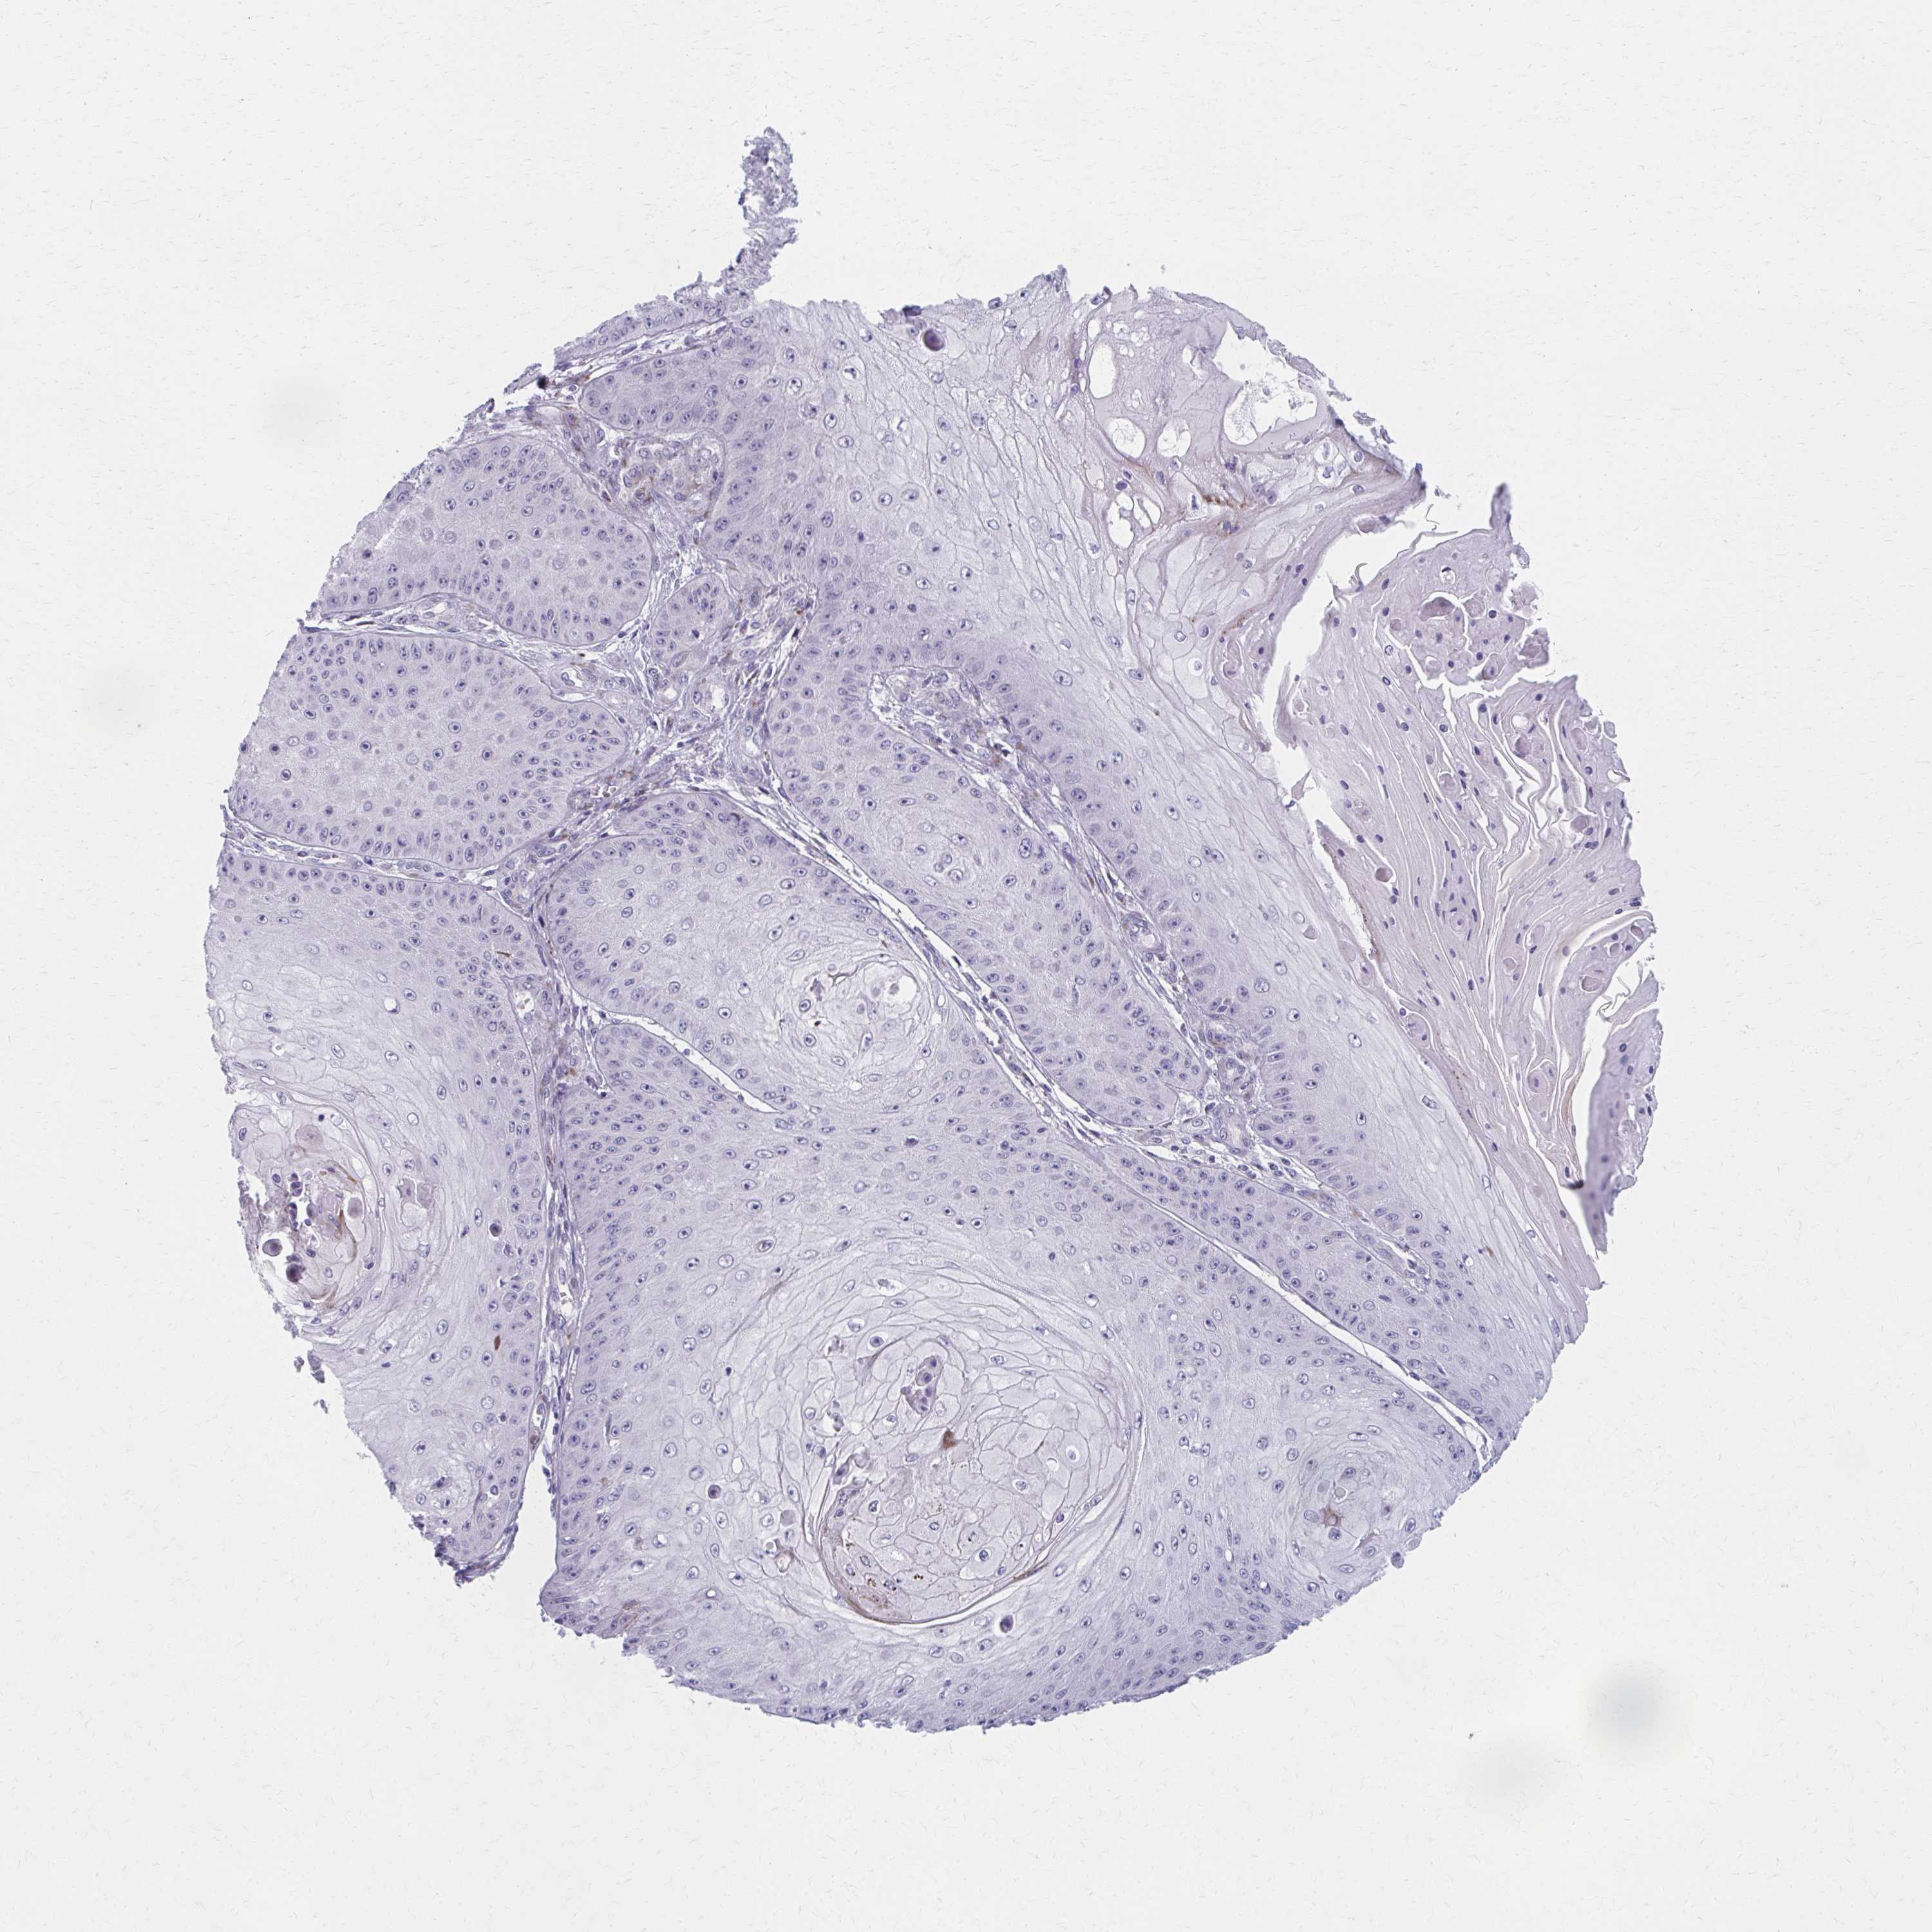

CANCER SKIN CANCER Show tissue menu

Basal cell and squamous cell cancer

SKIN CANCER - Protein expressioni

A mouse-over function shows sample information and annotation data. Click on an image to view it in a full screen mode. Samples can be filtered based on level of antibody staining by selecting one or several of the following categories: high, medium, low and not detected. The assay and annotation is described here.

Each image is clickable and will lead to virtual microscopy that enables deeper exploration of all samples and also displays staining intensity scores, fraction scores and subcellular localization as well as patient and tissue information for each sample.

Antibody HPA057771

Basal cell carcinoma

Squamous cell carcinoma, NOS